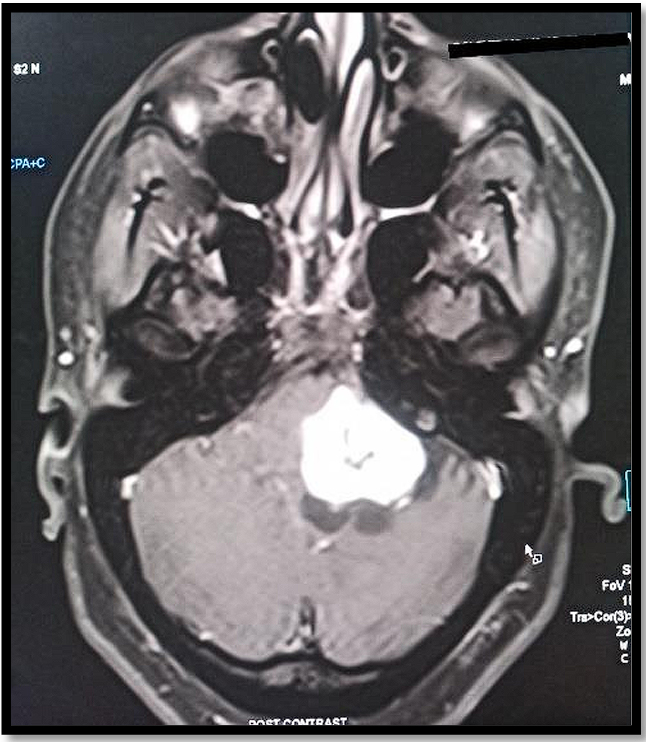

MRI revealed a left cerebellopontine angle (CPA) tumor suspected to be a vestibular schwanomma with extension into left internal acoustic meatus (Figures 2 and 3), and mass effect evidenced by buckling of pons, middle cerebellar peduncle, left cerebellar hemisphere and effacement of fourth ventricle (Figures 4 and 5).

Figure 2. T1 weighted MRI: hypointense lesion

Figure 3. T2 weighted MRI: hyperintense lesion

According to Isobe et al, Ancient Schwannomas are usually located deep in the head and neck, thorax, retroperitoneum and pelvis and extremities of elderly persons. MRI is the most useful technique for the evaluation of ancient schwannoma. Normal schwannomas show peripheral low intensity signal in T1W imaging and high intensity signal in T2W image.7 In contrary, ancient schwannomas show well circumscribed complex cystic mass with different enhancement pattern which mimics malignant tumors. Hence a strong suspicion of ancient vestibular schwannoma has to be considered as radiological imaging and histopathological features mimics malignancy.